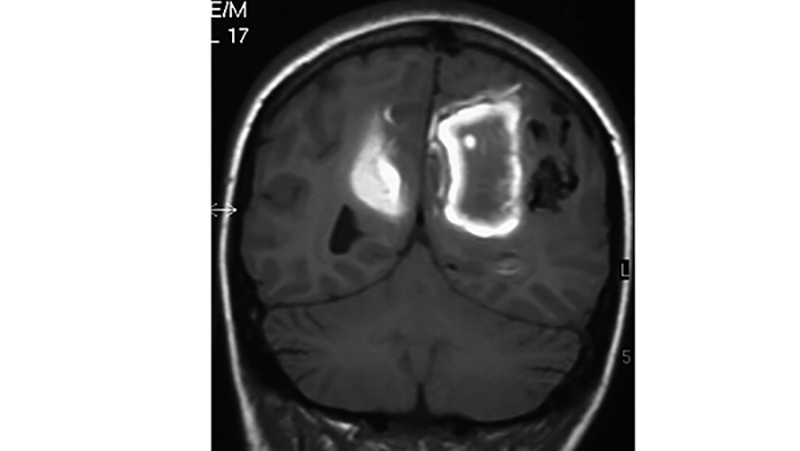

- Μαγνητική τομογραφία σε Τ1 ακολουθία, οβελιαία τομή. Ενδοεγκεφαλικό αιμάτωμα μετά από ρήξη αρτηριοφλεβώδους δυσπλασίας του αριστερού βρεγματικού λοβού σε κορίτσι ηλικίας 15 ετών.